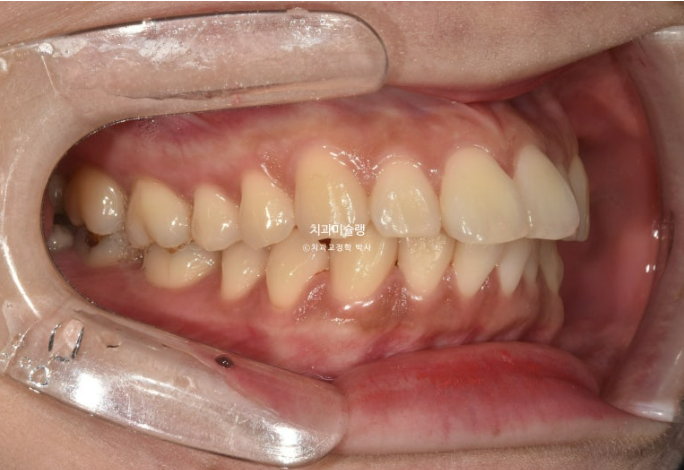

24년 8월까지 일년간 첫세트 48개 장치를 모두 낀 후 모습입니다.

24.08

중심선 불일치가 아직 조금 남았고, 가위교합은 모두 해소가 되었습니다.

앞니 뻗침도 개선이 되었고, 어금니 교합도 좋습니다.

혀쪽으로 쓰러져 있던 아래 큰어금니도 잘 섰습니다.